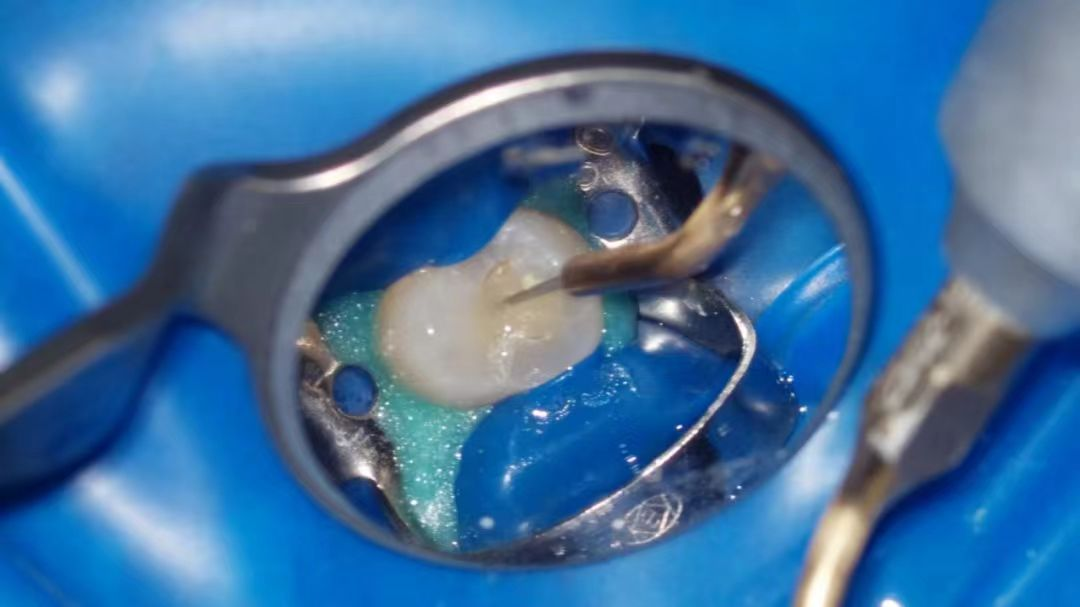

显微镜辅助下的超声荡洗